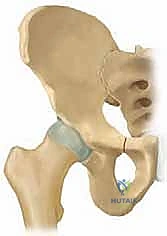

لفهم أهمية جراحة (TIO)، يجب أولاً فهم التشريح المعقد لمفصل الورك. يُصنف مفصل الورك على أنه مفصل كروي حقي (Ball-and-Socket Joint). تتكون "الكرة" من رأس عظم الفخذ (Femoral Head)، بينما يتكون "التجويف" من الحق (Acetabulum) وهو جزء من عظم الحوض.

في الحالة الطبيعية، يحيط التجويف الحقي برأس الفخذ بشكل شبه كامل، مما يوفر ثباتاً هائلاً أثناء الأنشطة اليومية مثل المشي، الركض، وحمل الأوزان. تعمل الغضاريف الملساء التي تغطي كلا السطحين على تقليل الاحتكاك، بينما تحافظ الأربطة القوية على بقاء المفصل في مكانه.

في حالات خلل التنسج، يكون التجويف الحقي ضحلاً جداً (غير عميق بما يكفي) أو مائلاً بزاوية غير طبيعية. هذا يعني أن "الكوب" لا يغطي "الكرة" بشكل كافٍ. نتيجة لذلك: